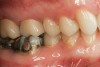

The milled and sintered zirconia substructure is fit to the SLA die model. The external surface of the zirconia substructure is air-abraded using Rocatec™ Soft (3M ESPE) to prepare it for fusion to the digital veneer. The digital veneer is carefully cut from the block holder and placed in distilled water for 1 minute to allow water to uniformly penetrate into the glass ceramic. The Lava DVS Fusion Porcelain is mixed in one of the 10 shades appropriate for the shade of the restoration and painted on the internal surface of the digital veneer. Additional fusion porcelain is placed on the external surface of the zirconia substructure, and the digital veneer is positioned over it. The excess fusion porcelain is expressed from between the two layers as the digital veneer is compressed to place over the substructure (Figure 15). The excess fusion porcelain is smoothed out at the margins, then fired in a porcelain oven. The final contours of the restoration are refined on the articulated SLA models. The final shade of the crown is influenced by the shade of the colored zirconia substructure, fusion porcelain, and the digital veneer. The fused crown can also be customized with surface stains and glazes (Figure 16). The case is returned to the dental office for delivery to the patient with a choice of adhesive or conventional cementation (Figure 17 and Figure 18).

Figure 16  Completely processed crowns.

Figure 16

Figure 17  Occlusal view of cemented crowns for teeth Nos. 2 and 3.

Figure 17

Figure 18  Facial view of the cemented crowns for teeth Nos. 2 and 3.

Figure 18